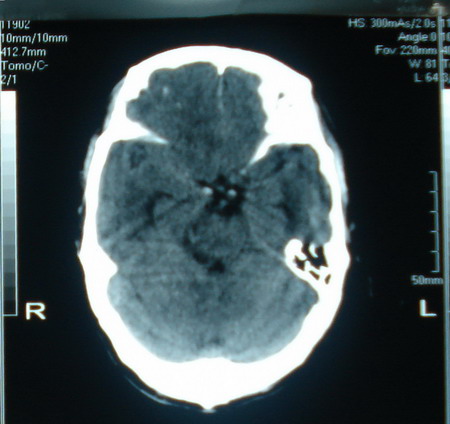

标题: CT13794:M63Y,头颅CT平扫 [打印本页]

标题: CT13794:M63Y,头颅CT平扫

男,63岁,头痛,呕吐,意识模糊一周。无发烧及感染史。

小肿瘤大水肿,考虑转移瘤

脑肿瘤 1 室管膜瘤 2 转移瘤

考虑为:胶质瘤可能性大,不排除转移瘤。建议:行进一步检查。

支持右侧丘脑恶性胶质母细胞瘤可能性大,建议增强进一步检查。